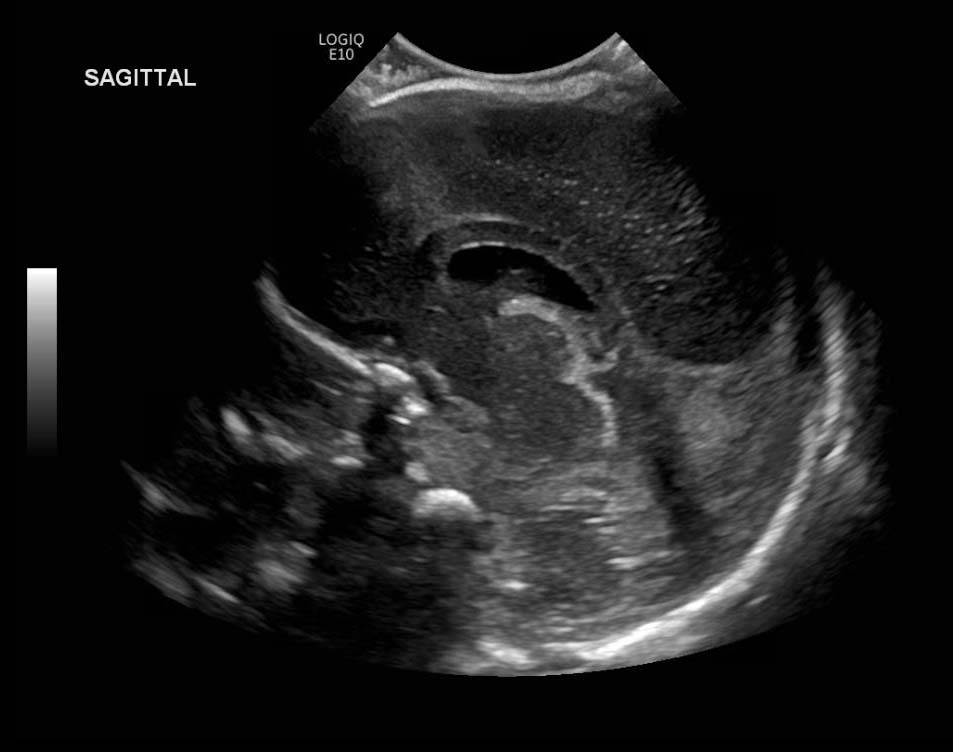

Age: 4 days (born at 24 weeks)

Sex: Male

Indication: Evaluate for germinal matrix hemorrhage

Grade 2 germinal matrix hemorrhage

Sample ReportLeft germinal matrix hemorrhage involving the caudothalamic groove and layering in the occipital horn of the left lateral ventricle without hydrocephalus (grade 2).

No abnormal brain parenchymal echogenicity or extra-axial collections.

Premature sulcation pattern.